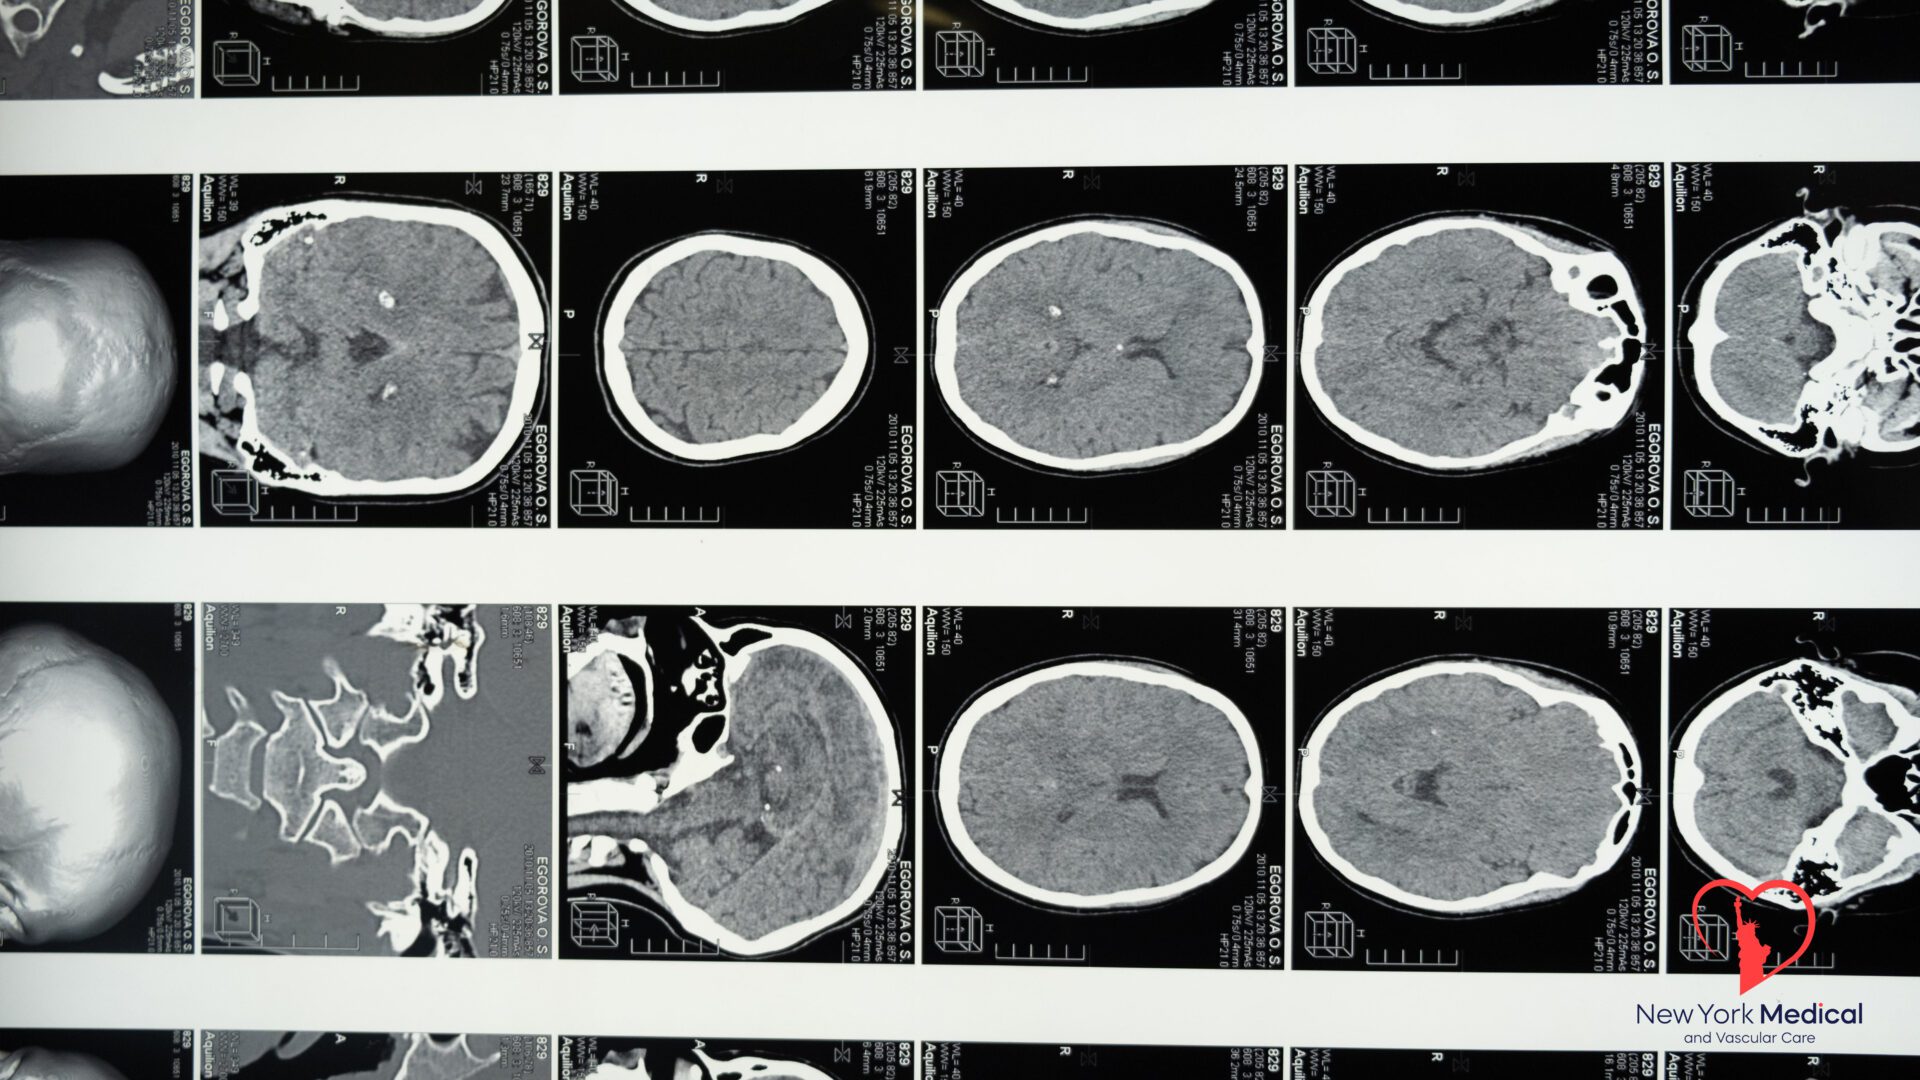

Advanced Imaging Techniques: Utilizing high-resolution MRI and CT scans allows for better visualization of cerebrovascular conditions, like arterial stenosis or aneurysms, which are precursors to strokes. These techniques enable early intervention.